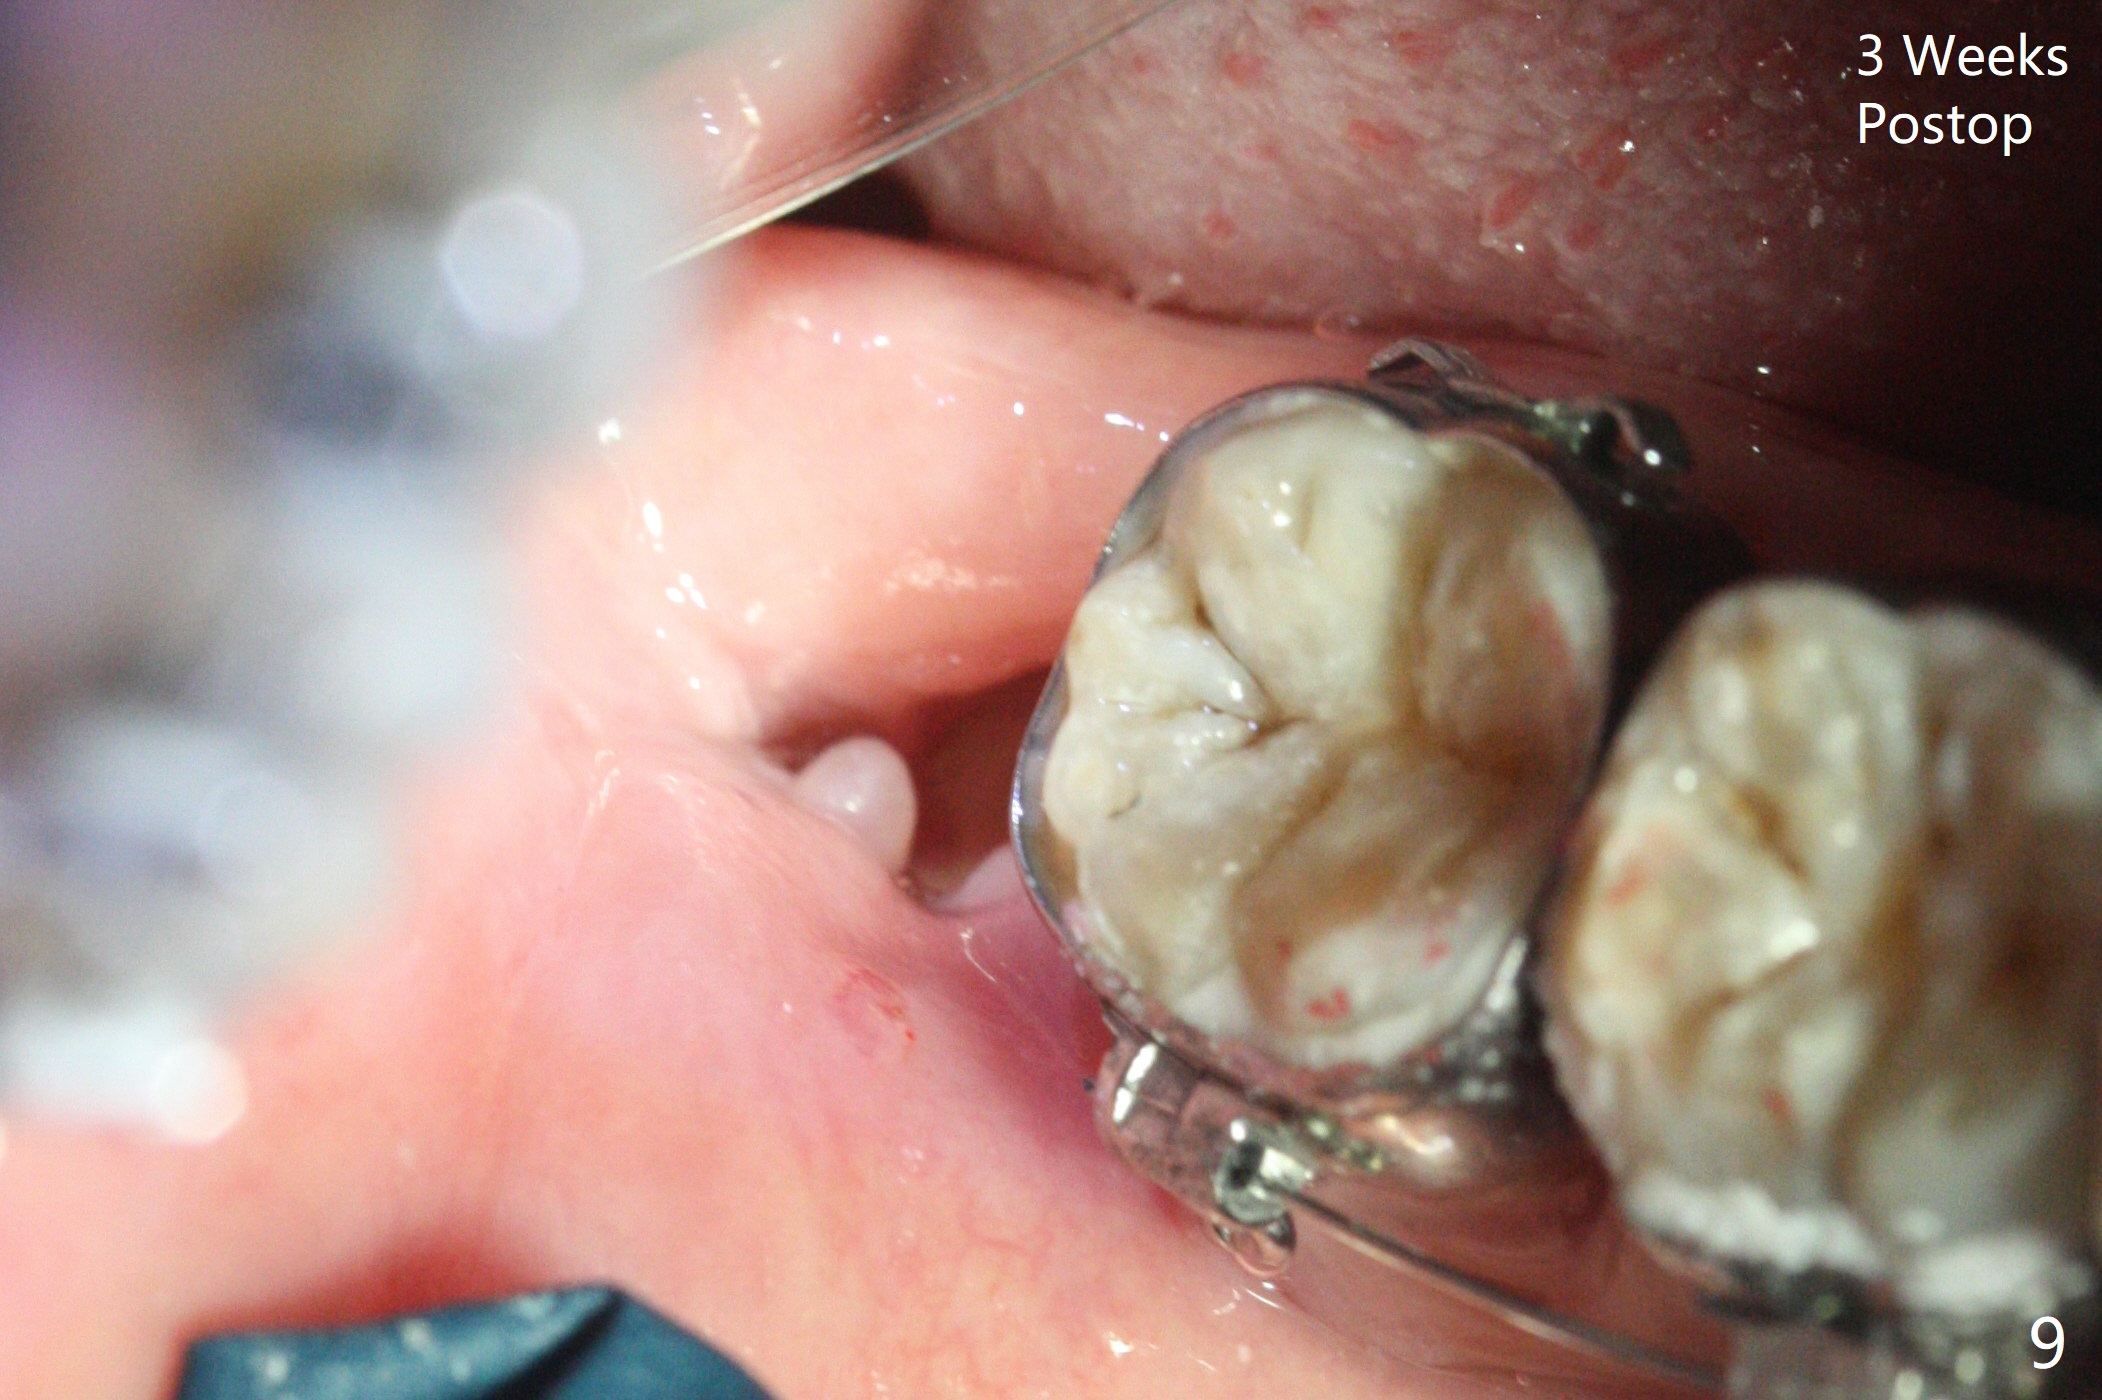

A 40-year-old man requests extraction of the teeth #17 and 32 (Fig.1). This case is designed to test that socket ossifies coronal when Collagen Plug is placed coronal. Release incision will be made both sides. Collagen plug will be placed at #32; none at #17. 4-0 PGA will be used to close the sockets. Photos will be taken immediate, 1 week, 1 month, and 3 months postop. PAs (sensor 1) will be taken immediate and 3 months postop. There is no wound dehiscence 1 week postop (Fig.6,7). The sockets reopen asymptomatic 3 weeks postop (Fig.8-11).